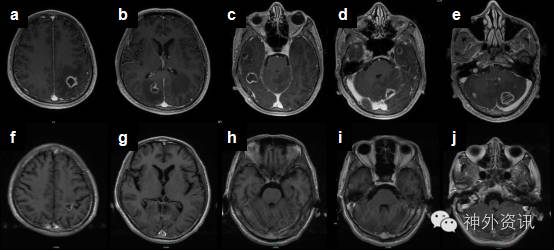

门诊进一步查PET-CT提示:①颅内多发病灶,左侧顶叶可见囊性灶,周围水肿效应明显,病灶中心及水肿带糖代谢减低,囊壁糖代谢稍增高(图2),右侧颞叶、顶叶、双侧小脑可见低密度灶,放射性摄取不高,考虑恶性病变;②右肺中叶内侧段炎症首先考虑,建议随访;③双颈部淋巴结、腹股沟淋巴结反应性增生考虑。

图2. PET-CT所示左侧顶叶病灶,考虑为囊性病灶,周围可见水肿带,周围正常脑皮质呈高代谢,SUVmax=15.1,囊壁糖代谢稍增高,SUVmax=3.7,病灶中心(粗黑色箭头)及水肿带糖代谢减低。

TE患者大多数血清抗弓形体抗体阳性,亦有血清学阴性的弓形虫感染报道[8]。脑脊液化验可以正常或轻度异常,抗体检测可能有助于诊断。通过留取脑脊液标本行PCR检测弓形体基因组中一条529bp的特征性片段,其诊断灵敏度为68.8%,但特异性高达100%[2]。TE在影像学上特征性地表现为多发环状强化病灶,周围伴有水肿和占位效应,MRI检查较CT更为敏感。DWI/ADC序列可能在鉴别TE和脑脓肿、原发淋巴瘤方面具有一定的价值,研究发现TE病灶核心部分未见弥散受限,ADC值较淋巴瘤更高[3]。SPECT和PET上则表现为低代谢病灶,可与肿瘤性疾病鉴别。本病例PET-CT可见左侧顶叶病灶中心低代谢,囊壁稍高代谢。颅内炎性病变糖代谢可呈不同程度增高,急性期一般代谢不高,如进入慢性期,转为肉芽肿性病变,代谢可明显增高,此时与恶性肿瘤不易区分,因此在解读PET-CT时,需结合患者具体病情,进行个体化分析。多数情况下,依据CD4+T淋巴细胞数,血清学检查,临床表现,以及特征性的影像学表现,即可拟诊TE并启动治疗,如果经验性治疗有效,便可确定诊断,仅仅在上述证据不足而导致诊断困难时才考虑开颅活检[1]。